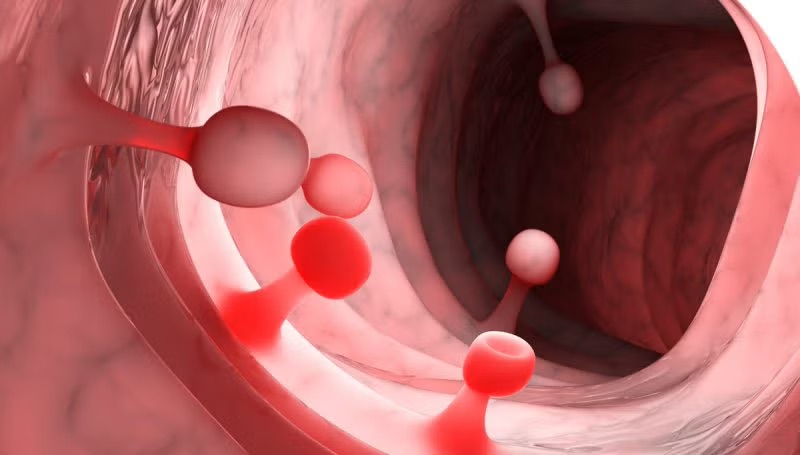

Las adhesiones intrauterinas son bandas de tejido fibroso que se forman dentro de la cavidad del útero, provocando que sus paredes se adhieran parcial o totalmente. Esta condición puede alterar la anatomía uterina normal y afectar la menstruación, la fertilidad y la salud reproductiva.

Estas agresiones pueden generar una cicatrización anormal, dando origen a las adherencias.

La histeroscopía permite visualizar directamente la cavidad uterina y evaluar el grado de las adherencias.